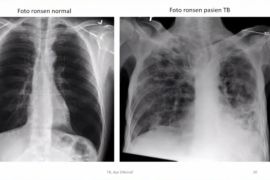

Djauddin menuturkan Pemprov Kalsel dengan Dinas Kesehatan kabupaten/kota menelusuri pengidap penyakit TBC yang berpotensi serius mempengaruhi paru tersebut, karena terindikasi banyak yang belum terdeteksi.

Djauddin mengungkapkan penanganan kasus penyakit TBC ini dilakukan serius, karena berdasarkan Indonesia menduduki nomor dua terbanyak kasus TBC di dunia setelah India.